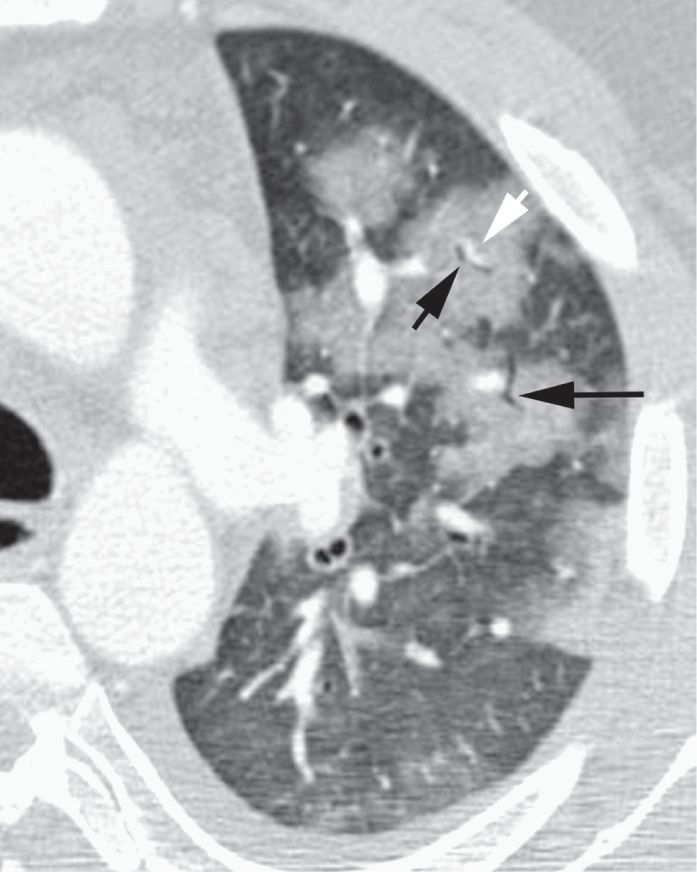

图2-4 实变,斑片状致密影

A、B. 支气管肺炎及小叶性实变患者增强HRCT显示单个小叶实变而周围邻近小叶正常,实变区小叶中心动脉( 白箭头) 和细支气管( 黑箭头);C. 冠状面CT 也显示斑片状实变影呈小叶性分布